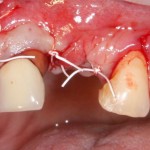

Для удаления зубов мы используем прямой элеватор и тонкие «корневые» щипцы-байонеты. Сама процедура удаления занимает около 10 минут:

Давайте внимательно посмотрим на состояние лунок центральных резцов после удаления:

Приемлемый фенотип (сочетание толщины и ширины участка жевательной десны) — это, конечно, приятно. Но гораздо важнее сосредоточиться на рисках, их на этот момент два:

— травматическое повреждение слизистой, вызванное удаление зубов связано с тем, что при хроническом воспалении слизистая оболочка теряет эластичность, поэтому легко рвётся. Такая ситуация создаёт серьёзную угрозу эстетическому результату лечения, в зависимости от того, насколько быстро десна придёт в норму.

— как и предполагалось после КЛКТ, утрата костной стенки привела к тому, что десна провалилась в просвет лунки левого центрального резца. Это еще больше усугубляет клиническую ситуацию.